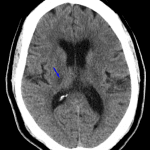

- Areas of hypoattenuation in the posterior limb of the right internal capsule, inferior left thalamus, right hemipons, and right cerebellar hemisphere

- Asymmetrically hyperdense appearance of the right internal carotid artery terminus and proximal right MCA

- Internal capsule lacunar infarct

Small vessel infarcts involving the posterior limb of the right internal capsule, inferior left thalamus, right hemipons, and right cerebellar hemisphere, which are age-indeterminate in the absence of prior imaging for comparison. Consider MRI for further evaluation if there is clinical concern for acute infarct.

Asymmetrically hyperdense appearance of the right internal carotid artery terminus and proximal right MCA, which may be artifactual or could represent thrombus. Recommend correlation with CTA.